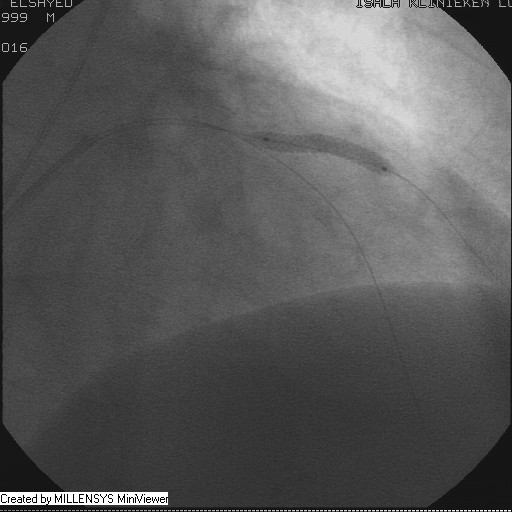

Patient transfered to Cardiac Catheterization Laboratory, coronary angiography showed atherosclerotic coronaries but without significant lesions, especially LAD that was patent with TIMI 3 flow (Figure 1- 5). Re-evaluation of the Angiography showed a small stump that can be for an occluded 1st diagonal (Figure 2a), at that level the LAD has a non-significant lesion.

After crossing with the PTCA wire, a minimal flow started to appear in the diagonal branch (Figure 6), then LAD was wired, then a 2x15mm Balloon was used to pre-dilate (Figure 7,8), a big diagonal branch appeared with proximal thrombotic tight lesion (Figure 9), the diagonal angle to LAD was about 90 degree (Figure 10), so provisional stenting done to diagonal from its ostium with 3x20mm PROMUS ELEMENT PLUS DES (Figure 11,12), with good final result (Figures 13&14).

Figure 2A